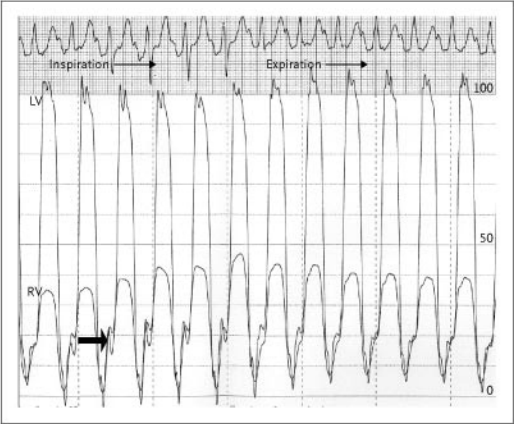

El paciente fue sometido a cateterización cardíaca derecha e izquierda lo que mostró los siguientes valores hemodinámicos: presión auricular derecha media 20 mm Hg; presión ventricular derecha 48/20 mm Hg; presión de la arteria pulmonar 48/22 mm Hg (presión media 30 mm Hg); presión capilar pulmonar-wedge 20 mm Hg; presión ventricular izquierda 130/20 mm Hg; presión aórtica 130/80 mm Hg. Las presiones diastólicas ventriculares derecha e izquierda tomadas en forma simultánea mostraron igualamiento y un patrón de onda “dip-plateau”; las medidas simultáneas de las presiones sistólicas ventriculares mostraron discordancia, hallazgo que es compatible con interacción ventricular aumentada (Figura 3).

Figura 3. Trazado hemodinámico simultáneo de presiones de ventrículo derecho (RV) y ventrículo izquierdo (LV), mostrando discordancia de las presiones sistólicas durante la respiración (flechas finas), e igualación de las presiones diastólicas (flecha gruesa).